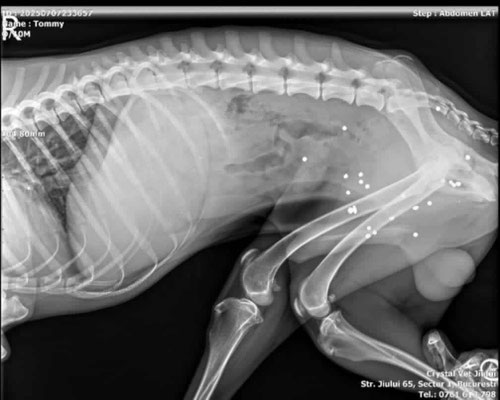

Tomi haben wir Mitte April 2025 verletzt und völlig abgemagert am Strassenrand eingefangen. Das Röntgenbild zeigte, dass der Körper des jungen Rüden voller Schrotkugeln war. Die an gefährdeten Stellen wurden in der Klinik entfernt, die anderen wurden belassen. Es resultierte eine Nervenschädigung insbesondere am linken Hinterbein, welche zu einer Atrophie und einer Hyperextension führte.